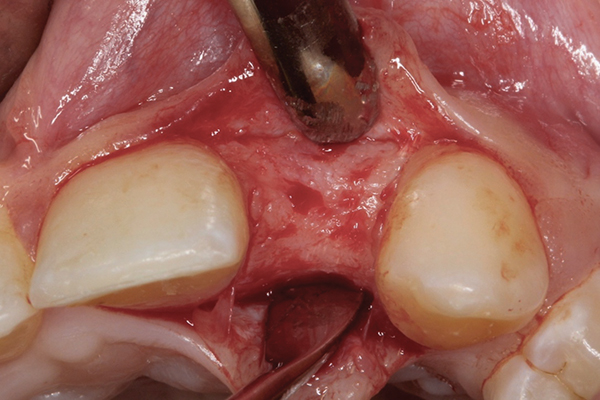

When the patient was age 17 years and 5 months, a cone-beam computed tomography (CBCT) scan30 was taken that revealed she had only 4.5-mm thickness of buccal/palatal alveolar ridge. The periodontist recommended lateral ridge augmentation to provide an additional 3 mm to 4 mm to achieve a stable long-term result.22,31 A root concavity on fused teeth Nos. 7 and 8 was also detected, which was thought to pose a complication for achievement of optimal gingival health.11 Alveolar bone augmentation of the buccal ridge at site No. 10 was performed. Following 6 months of healing, the second lateral cephalometric radiograph was taken by the orthodontist to verify cessation of somatic growth.29,31-33 Alginate impressions were taken by the prosthodontist to construct a surgical stent,34 and the final treatment plan was confirmed. As a result of the esthetic success achieved by the interim composite restoration, a lithium disilicate veneer35 using gingival porcelain to restore the missing interproximal papilla was proposed for fused teeth Nos. 7 and 8. The patient also requested a veneer for the adjacent central incisor, tooth No. 9. A ceramic implant crown and custom abutment were planned for site No. 10.

When the patient was 18 years old, an implant was placed in site No. 10 with no complications (Figure 9 and Figure 10). Three months later, a periapical radiograph was taken, the implant was torque tested, and a healing abutment (3 mm by 4 mm by 4 mm) was placed.

Fig 9 and Fig 10. An implant placed in site No. 10.